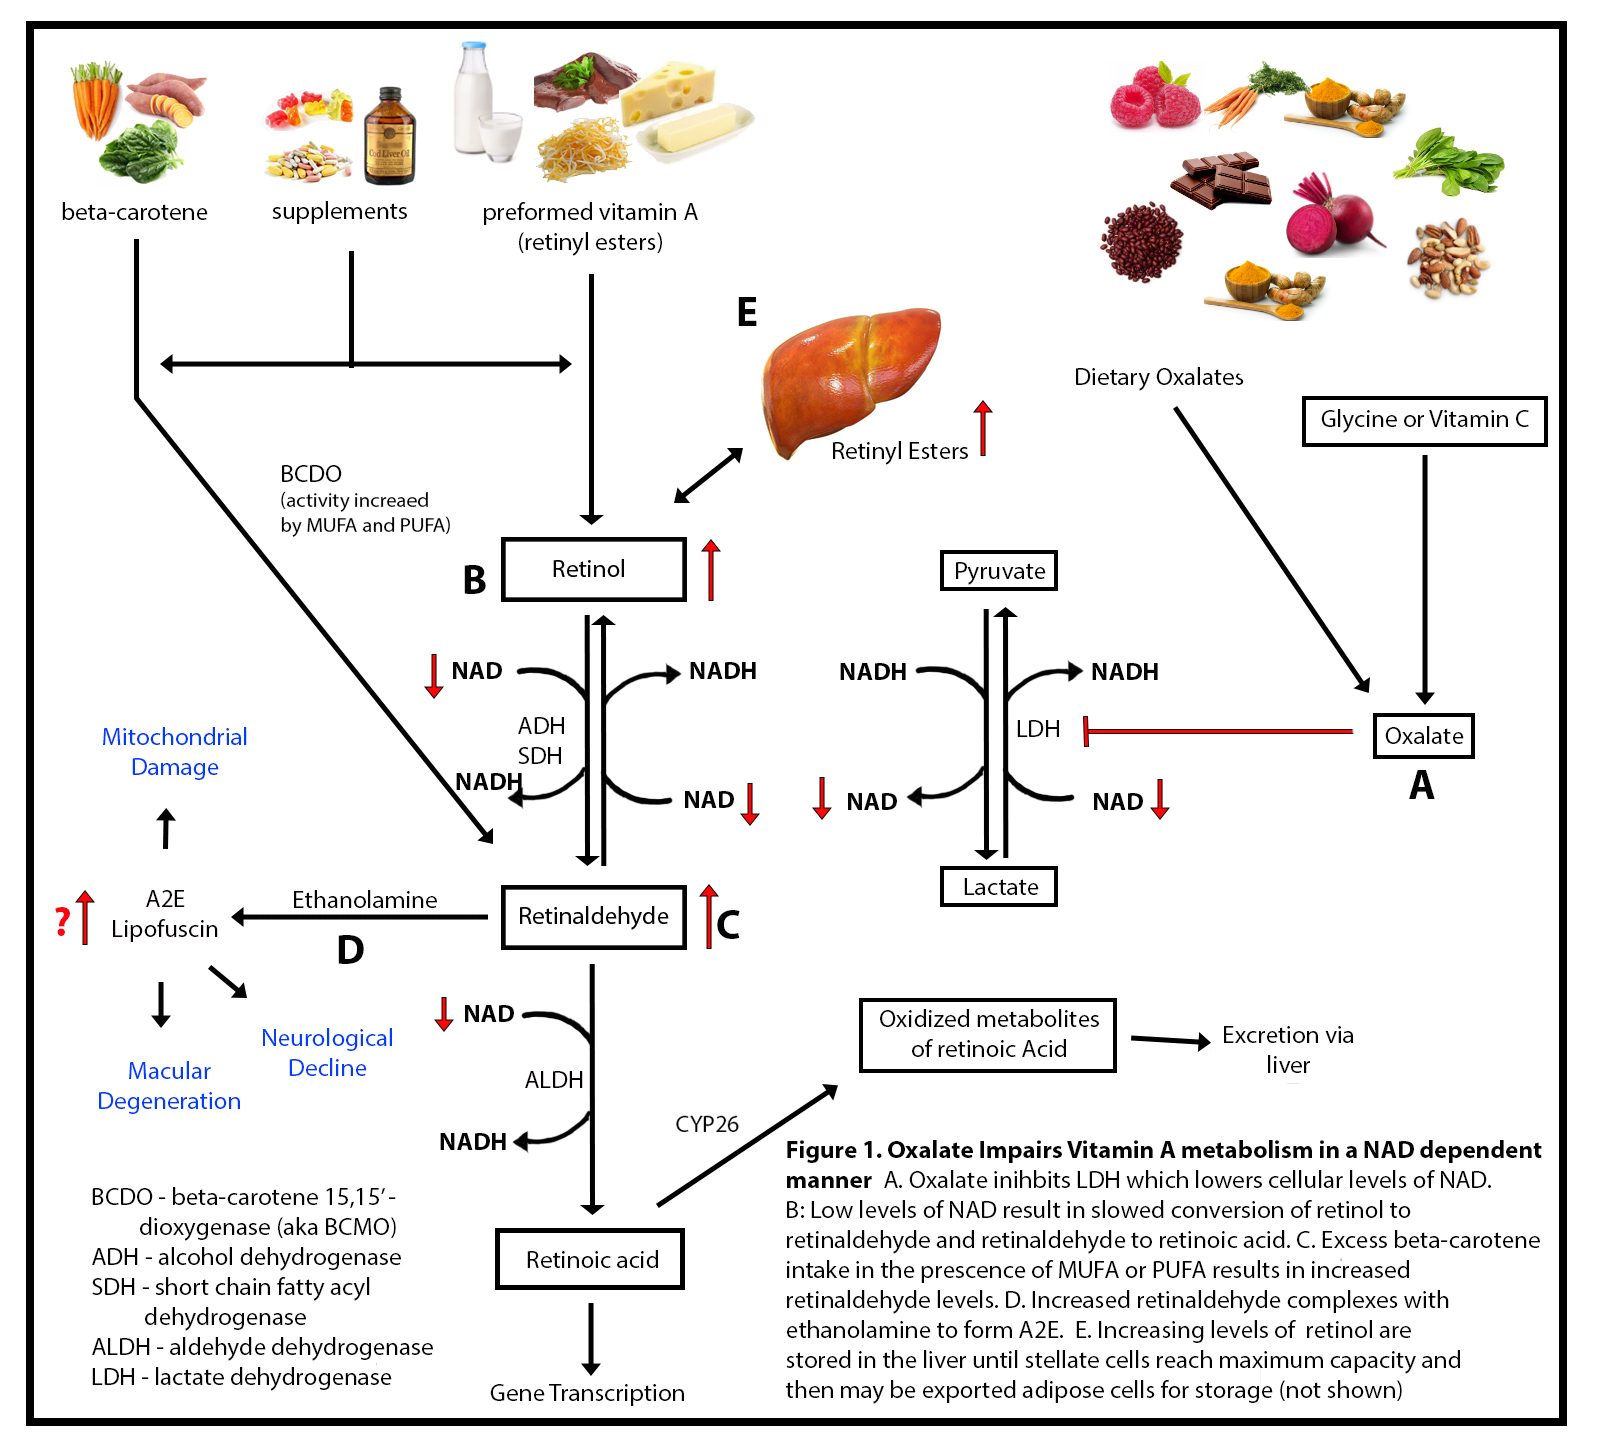

There is a truism in the sociology of occupational knowledge: “If all a doctor has is a hammer, then everything becomes a nail”. All modern medicine relies on overkill dosages of drugs or surgery as the standard of care (Jennifer Daniels, MD, The Lethal Dose, 2013). There are no drugs or surgery that can alleviate the symptoms of poisoning from a natural pesticide found in plant foods but also produced in the liver. With this professional void, treating oxalosis has mainly been left to nutritionists. So, if you ask a nutritionist about oxalates, you will get a predictable answer to reduce oxalates in your diet. This is insufficient because most oxalates are produced by poor metabolism in the liver. Oxalate is a natural pesticide found in plant foods, but also is internally produced mainly from fungus and vitamin C (see How Oxalates Ruin Your Health). Oxalosis manifests as a syndrome of three main symptoms: oxalate crystals in tissues and kidney; histamine, mucous attack in nasal passages; and pseudo-gout mainly from acidity and eating cooked meat.

Endogenous Oxalates Mainly Begin in the Liver

First, I learned that calcium is needed as a co-valent chemical binder to oxalate before meals to eliminate oxalate through the bowel or oxalic acid through with urine through the kidney. Secondly, I learned that plant foods like spinach, almonds, chocolate, and soy and were loaded with toxic levels of oxalates, a natural pesticide that protects plants from insects, worms, and herbivores. I also learned that high doses of synthetic Vitamin D (10,000 mg/day as a steroid) without Vitamin K2, could also lead to kidney stones and oxalosis. An iron deficiency may come into the picture as discussed below.

My thesis is that internally produced oxalate is systemic and organic. It mainly manifests oxalosis (oxalate poisoning) and is produced in the liver, not solely from dietary oxalate, which can be managed with modest palliative measures. Oxalosis comes from poor elimination in the liver and not entirely from the food we consume. It is an interaction between the two in a feedback loop. I believe that the conventional approach to oxalosis, e.g. reducing the consumption of high oxalate foods, does not significantly reduce internal oxalate production, and thus, is merely palliative.

The motivation for this paper is that I could find no satisfactory explanation of the mechanism of action for endogenous oxalate other than vague references that it is produced in the liver, while dietary oxalosis happens in the kidney. Hereinabove I have hypothesized a plausible explanation of oxalosis from the liver from poor protein metabolism and oxidation. Since science is not just about finding evidence, but also about attempting to falsify a hypothesis, I am throwing this hypothesis out there for open refutation and clarification.